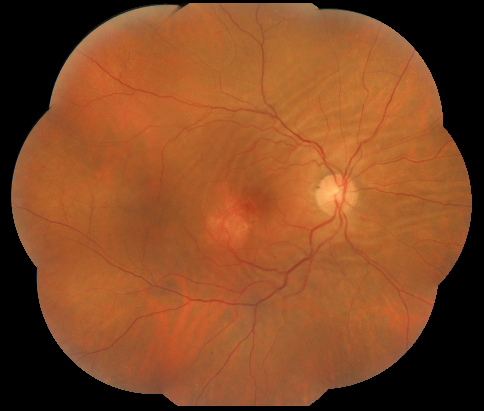

Choroidal folds in the posterior pole of the right eye associated with an area of atrophic and pigmentary changes (1 disc diameter in size) located inferotemporal to the fovea

| current | 10:15, November 9, 2020 | 484 × 411 (377 KB) | Manuel.Marques (talk | contribs) | Choroidal folds in the posterior pole of the right eye associated with an area of atrophic and pigmentary changes (1 disc diameter in size) located inferotemporal to the fovea |